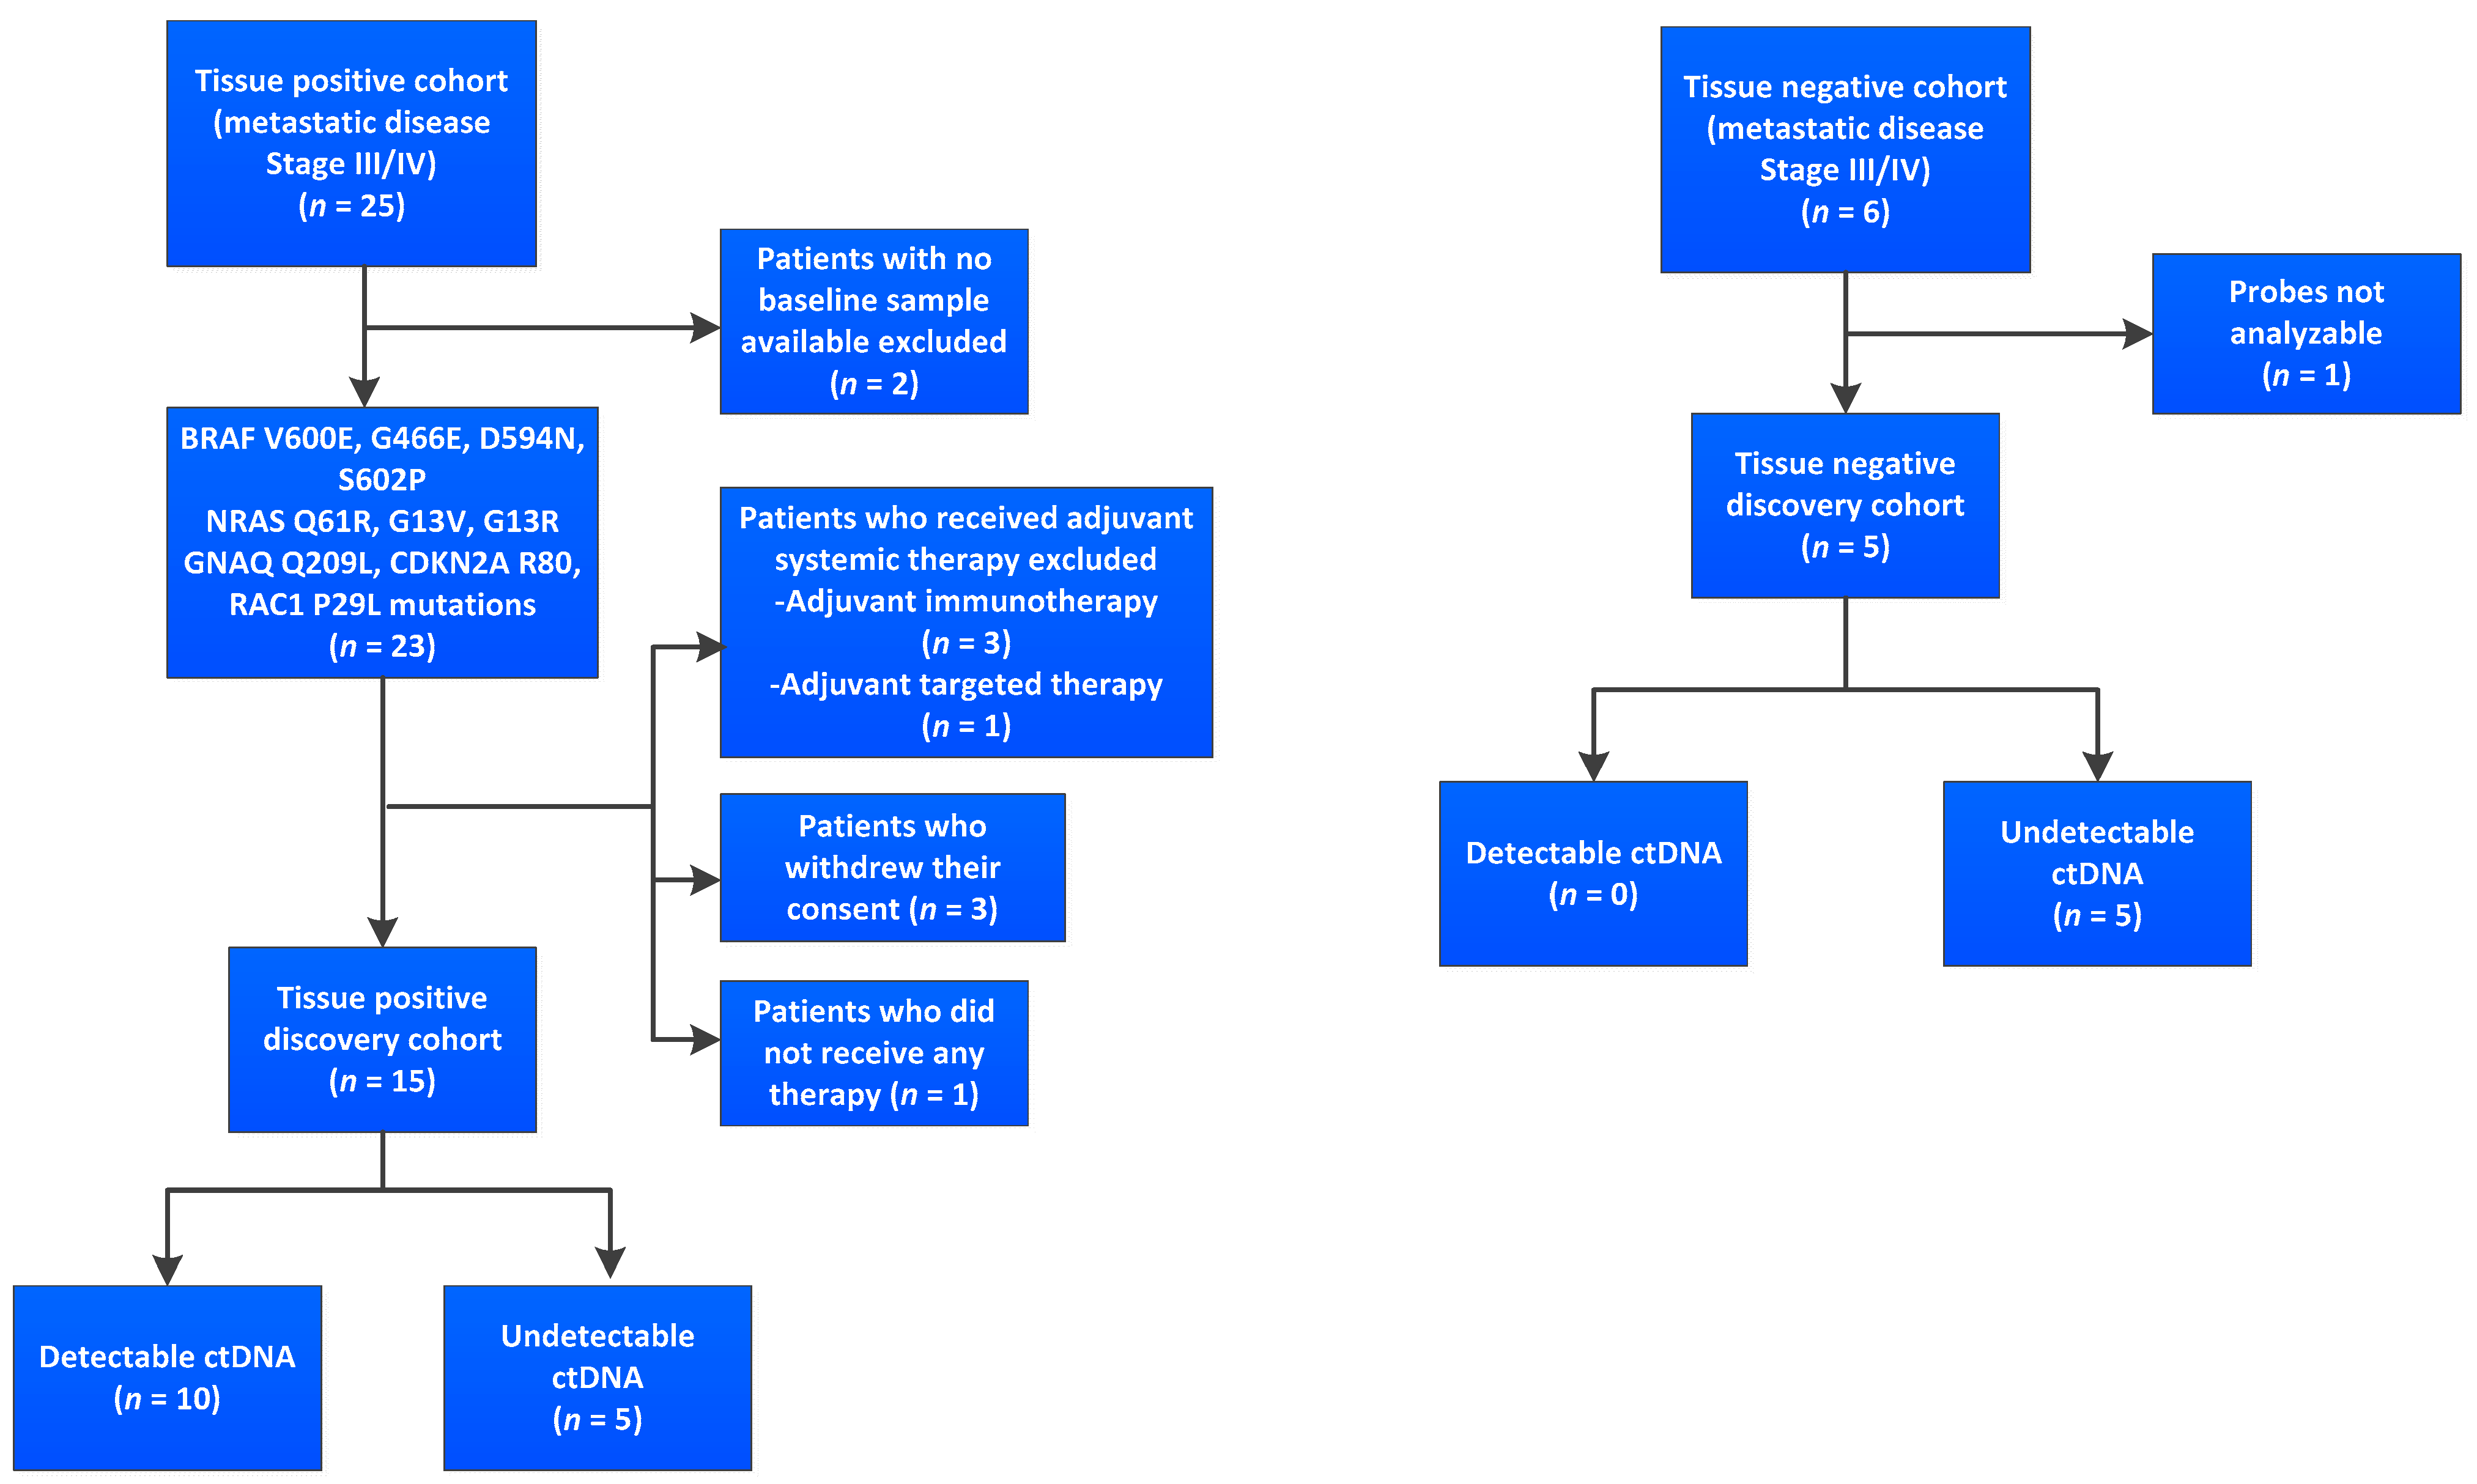

3.1. Cohort and Sample Characteristics